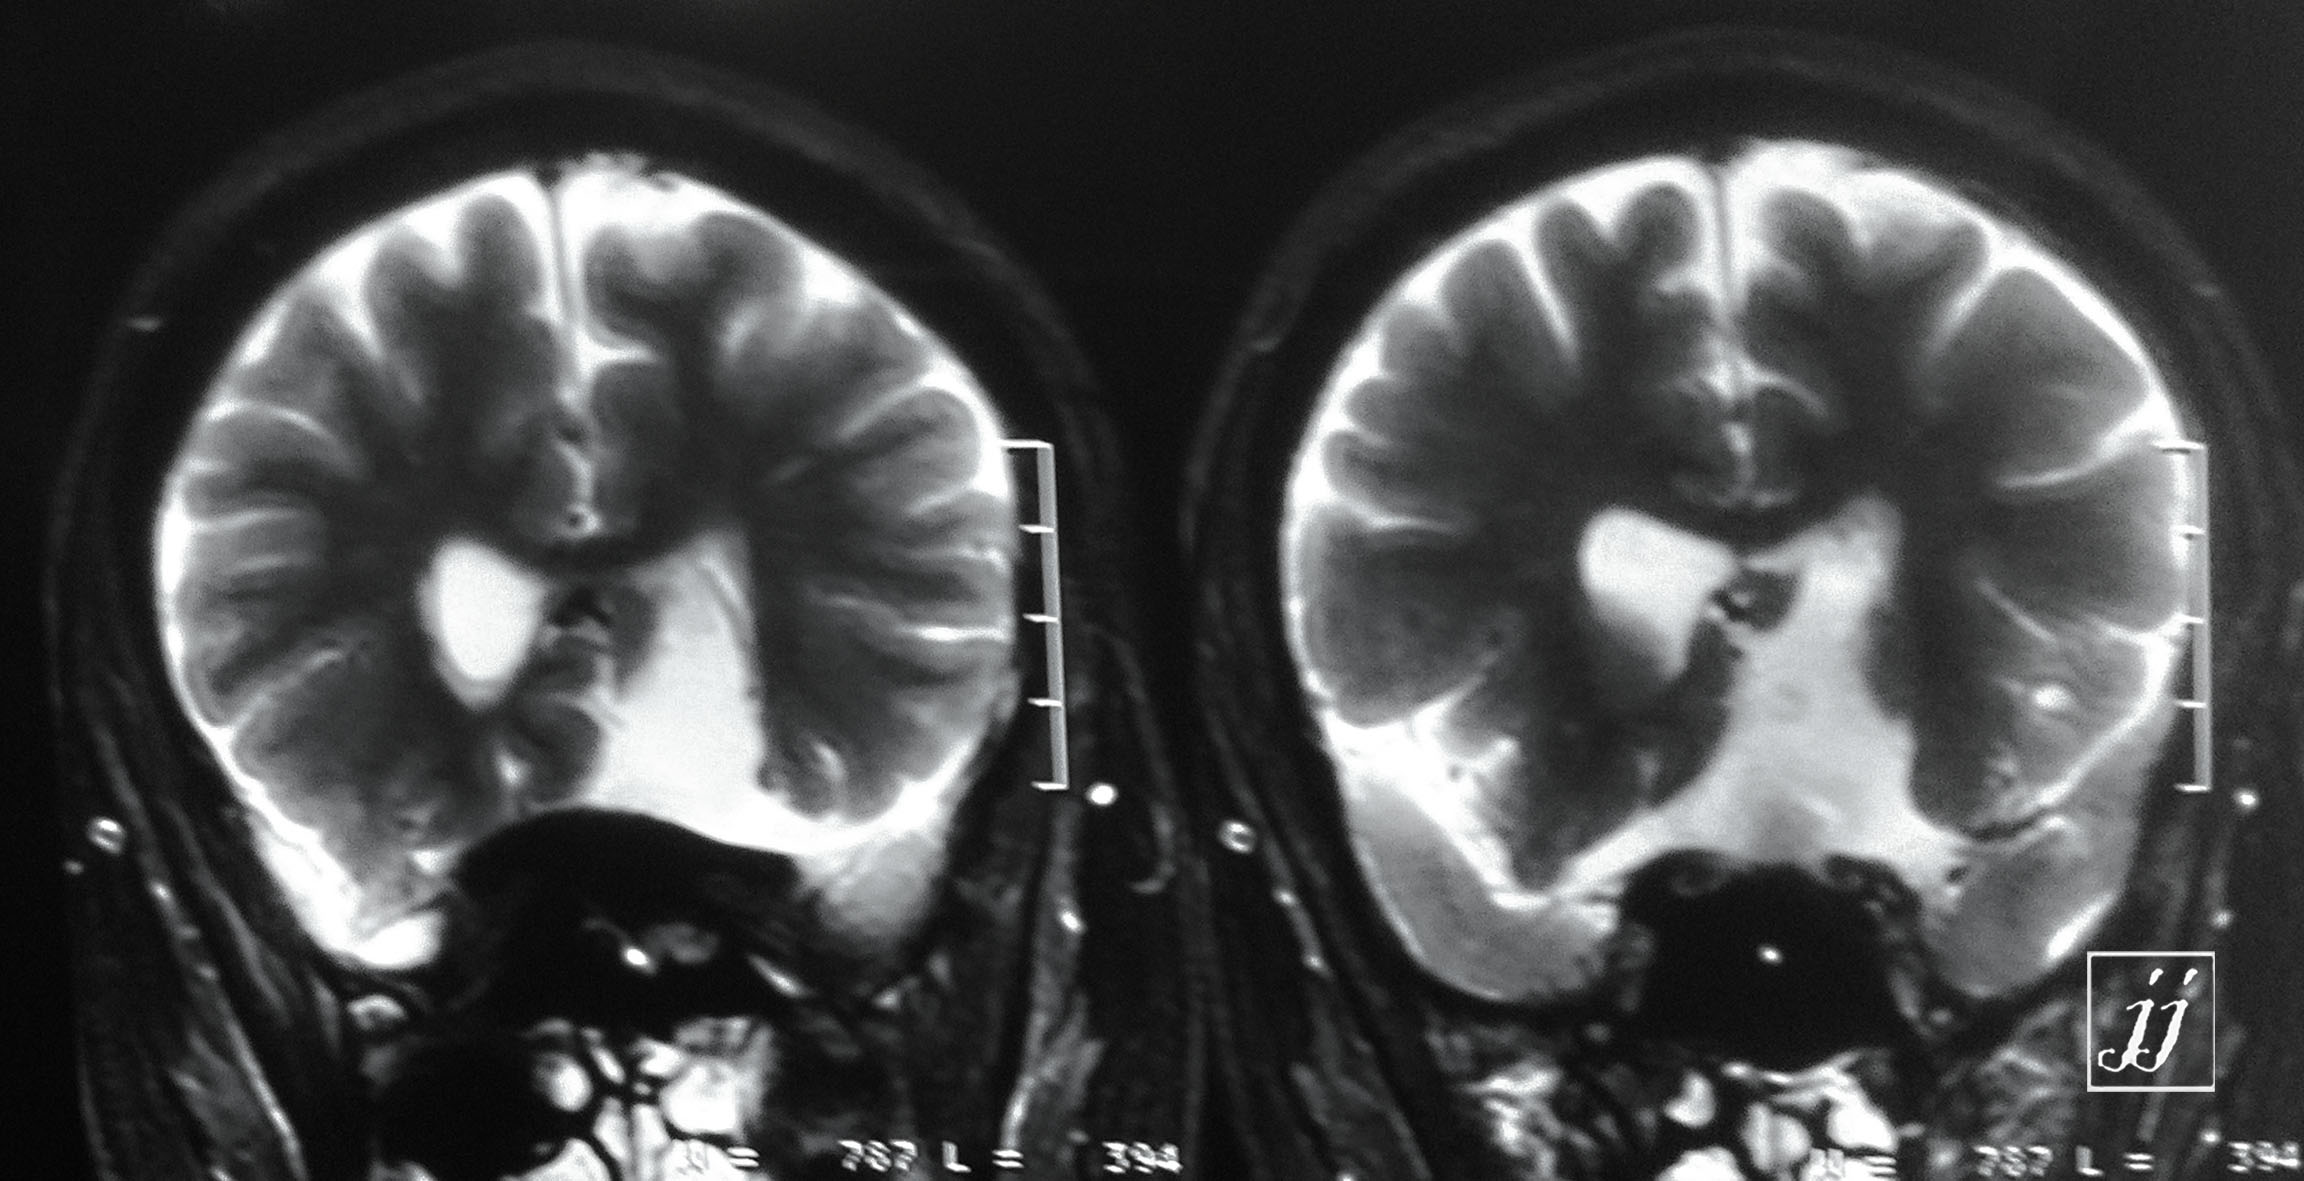

Brain- opac material in cisterns (5)